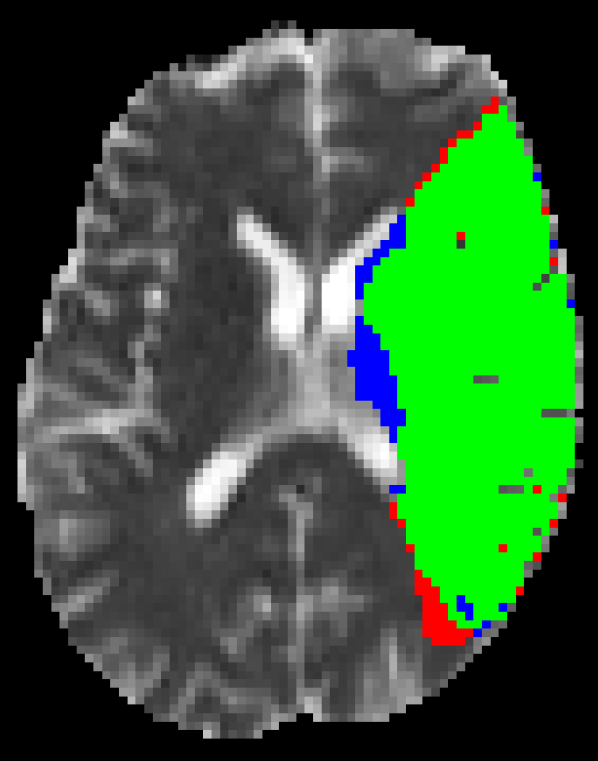

Representative examples of the qualitative results from the proposed method can be found in Figure 4. Cases 9 and 15 represent the overall results of the proposed methodology, correctly detecting the lesions in most cases with an outline that approximates the provided gold standard. Among the observed limitations are inaccurate borders and over/under segmentation of certain regions. For instance, in case 5 the lesion was undersegmented due to a heterogeneous appearance of the gold standard lesion while in case 13 two false positive lesions are detected due to the previous existence of chronic stroke lesions with a similar appearance.

Refer to caption

(a) Case 5

(b) Case 9

(c) Case 13

(d) Case 15

Figure 4: Output segmentation masks of representative cases from the training images of ISLES 2015 SISS dataset. On all images, true positives are denoted in green, false positives in red and false negatives in blue.